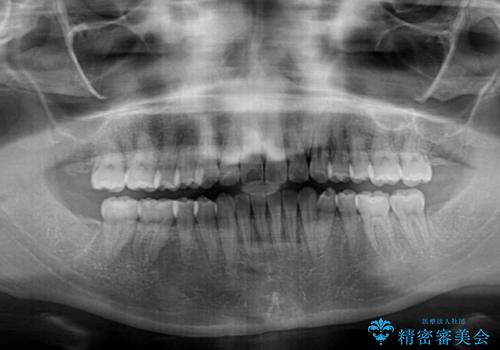

- 上下のデコボコを改善したいとのことで来院された患者様です。

近々妊娠する予定であり、極力短期間で治療したいとのことで、ワイヤー装置による非抜歯矯正治療を行うこととしました。

治療開始後すぐに妊娠され、つわりと闘いながらの矯正治療となりました。

上下顎でゴムかけを行ったのですが、早く終わらすためにしっかりと装着していただき、無事出産前に装置を外すことができました。